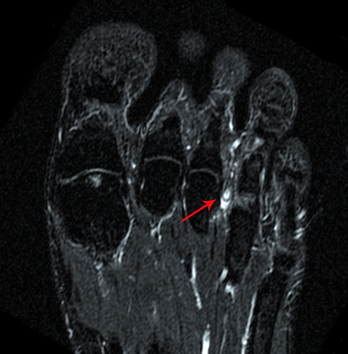

▶核磁共振: 相较于彩超,核磁共振更具优势。

图5:核磁共振清晰显示跖间神经瘤(红色剪头)